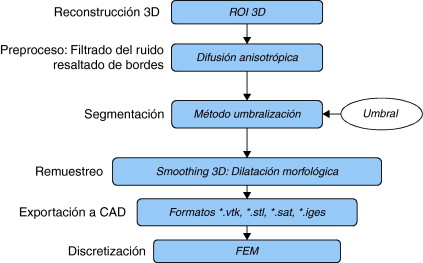

El problema de obtener modelos geométricos a partir de imágenes médicas implica la utilización de un conjunto de rutinas de procesamiento aplicadas a la matriz 3D de las imágenes médicas a lo largo de varias etapas de procesamiento. En la figura 1 se observan las cinco etapas propuestas con las herramientas de software utilizadas en cada una de ellas, las cuales son: (1) etapa de lectura y reconstrucción, en la cual se implementó una rutina para obtener una imagen 3D de dimensiones m × n × o obtenida por el apilamiento paralelo de o cortes ortogonales (axial, coronal o sagital) del mismo tamaño de m × n pixels , donde cada elemento de la matriz representa un valor de intensidad de gris calculado por la interacción de la radiación en el tejido. (2) Preproceso, en la cual se aplicaron rutinas de suavizado de ruido y realzado de bordes, de este modo se mejoró la calidad de las imágenes, preparándolas para la siguiente etapa. (3) Segmentación, en la cual se utilizaron rutinas de extracción del volumen de los tejidos u órganos de interés. (4) Remuestreo, donde se emplearon rutinas de posprocesamiento para suavizar las superficies y eliminar elementos no conectados presentes en los volúmenes segmentados. (5) Exportación de modelos, para lo cual se implementaron rutinas para almacenar los volúmenes obtenidos en formatos legibles por herramientas de visualización médica y CAD, en las cuales se visualice en sólidos, superficies, mallas, etc.

Figura 1. Esquema de procesos y rutinas implementados en una herramienta de procesamiento de imágenes médicas desarrollada en MATLAB [13] . |

Para la obtención de los modelos geométricos y la interacción con los algoritmos de procesamiento considerados en este trabajo, se desarrolló una herramienta computacional [13] bajo la plataforma de MATLAB [12] , en la cual se integraron las rutinas por etapas (fig. 1 ).

A continuación se describen los algoritmos de procesamiento considerados por cada una de estas etapas, y como fueron implementados en este trabajo.